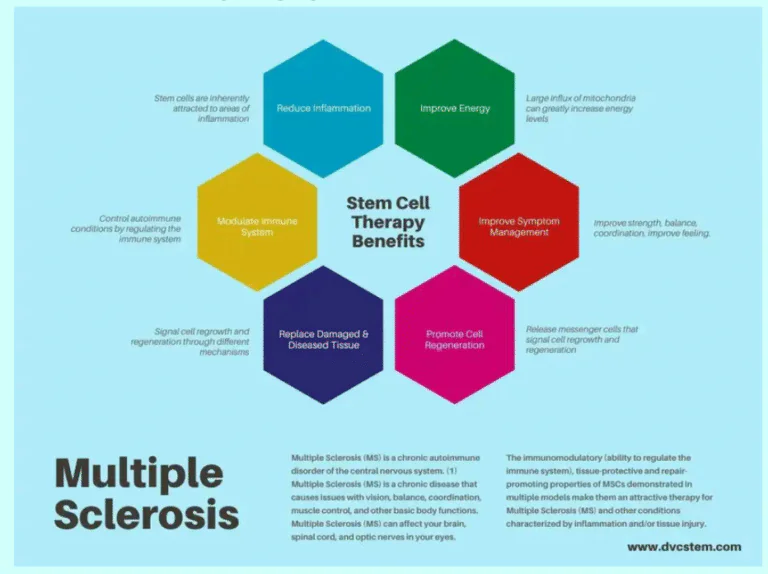

MULTIPLE SCLEROSIS

“Strengthening the nervous system supports long-term stability.”

Definition

Multiple sclerosis is an autoimmune disease where the immune system attacks the protective covering of nerves. This disrupts communication between the brain and body.

Common Symptoms

- Numbness

- Weakness

- Vision problems

- Balance issues

- Fatigue

Diagnostic Tests

- MRI brain and spine

- Neurological examination

- Lumbar puncture if required

- Blood tests for autoimmune markers

How Stem Cell Therapy May Help

Stem cell therapy may help regulate immune activity and support nerve repair. It may reduce inflammation and slow disease progression in selected cases.

Procedure

- Neurological assessment

- Imaging review

- Immune function screening

- Controlled regenerative therapy

- Rehabilitation and physiotherapy

- Regular monitoring